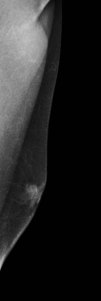

Se le realiza ampliación de estudio de mamografía, ambas mediolaterales. Imágenes 10 y 11:

Observamos claramente contorno nodular de la mama izquierda.